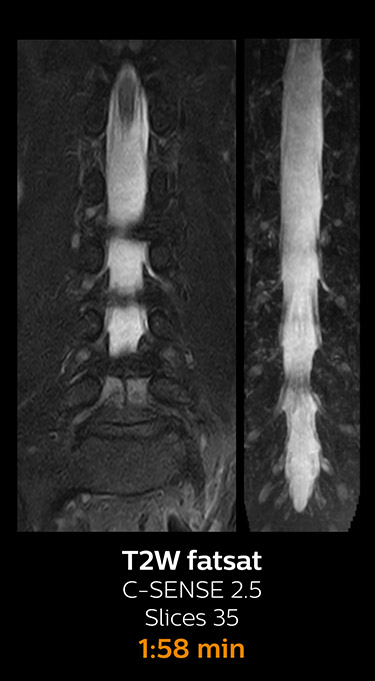

Fast MRI of lumbar spine

With Compressed SENSE, the scan time for the routine lumbar spine examination at KNC was reduced from 11:41 to 8:17 minutes,

which corresponds to 34% reduction.

MRI examination of lumbar spine with Compressed SENSE

MRI examination of the lumbar spine with Compressed SENSE

Ingenia 3.0T CX

Scan time 8:17 min. (was 11:41 min. without Compressed SENSE)